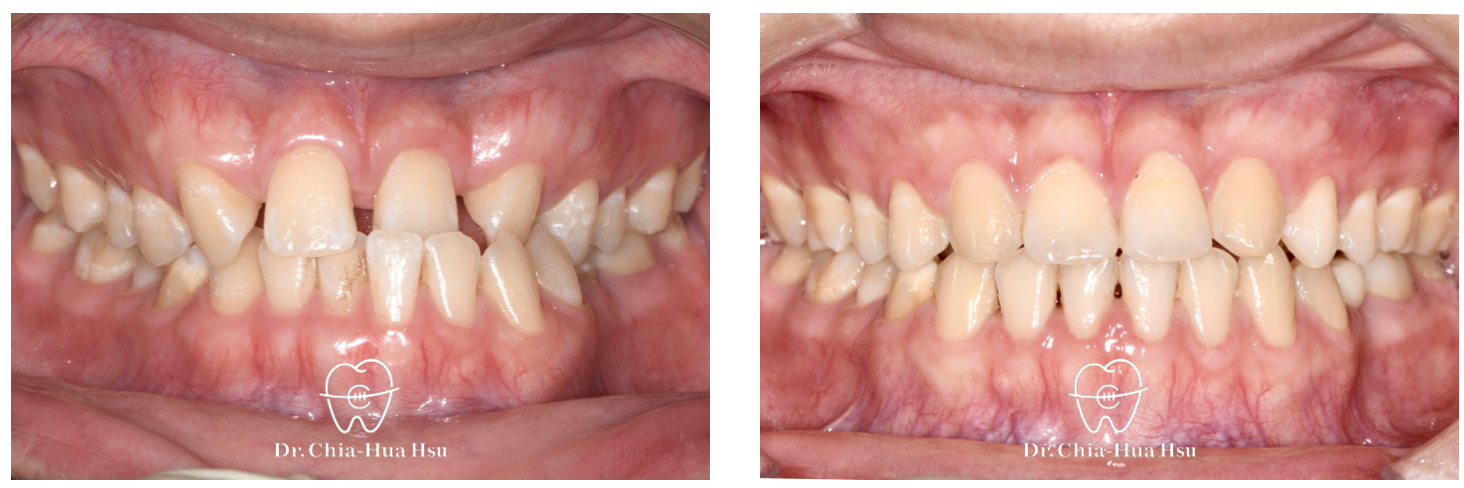

• 病患主訴:在意門牙牙縫和齒列不正。

• 問題分析:患者除了門牙牙縫、齒列不正問題,有先天性缺失上顎雙側側門牙兩顆以及左下第二小臼齒,並且左下方有滯留的乳臼齒,治療難度高。

• 治療方式:使用傳統金屬矯正器,並搭配拉口內橡皮筋的方式來讓上顎後排牙齒往前移動,以關閉缺牙縫隙。

• 治療結果:改善缺牙、縫隙,以及上下顎咬合關係,左下乳臼齒拔除後以一顆植牙重建。